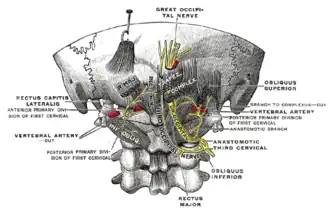

Posterior primary divisions of the upper three cervical nerves. (Great occipital nerve labeled at center top.) | |

The greater occipital nerve is a nerve of the head. It is a spinal nerve, specifically the medial branch of the dorsal primary ramus of cervical spinal nerve 2. It arises from between the first and second cervical vertebrae, ascends, and then passes through the semispinalis muscle. It ascends further to supply the skin along the posterior part of the scalp to the vertex. It supplies sensation to the scalp at the top of the head, over the ear and over the parotid glands.[1]

Structure

The greater occipital nerve is the medial branch of the dorsal primary ramus of cervical spinal nerve 2. It may also involve fibres from cervical spinal nerve 3.[2] It arises from between the first and second cervical vertebrae, along with the lesser occipital nerve. It ascends after emerging from below the suboccipital triangle beneath the obliquus capitis inferior muscle. Just below the superior nuchal ridge, it pierces the fascia.[2] It ascends further to supply the skin along the posterior part of the scalp up to the vertex.[2]